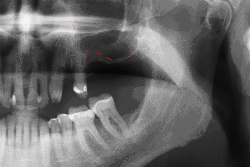

- с помощью рентгенографии изучаются качество и плотность костной ткани;